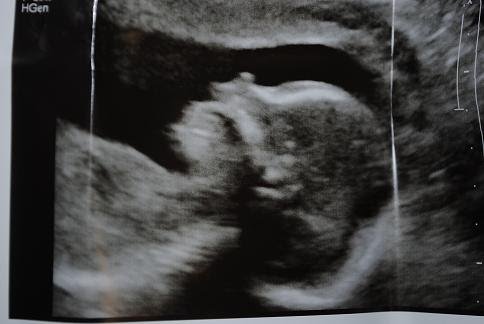

Today was my 20 week ultrasound. Despite the fact that I was exhausted from my friend Leigh’s wedding last night (Orthodox Jewish weddings are fun but oy! The food, the dancing!) I had a hard time getting to sleep. I was excited, because today was the day that I would find out the gender of my mystery baby.

During the course of the exam, the mystery baby yawned and pointed an accusatory finger at myself and Susan, the technician. Yes, Susan is her real name. She has no kids and one male cat. I found this out while I was bored out my mind looking at my fetus’ kidneys.

Then the moment of truth finally came. Without warning Susan announced that…the umbilical cord was between the baby’s legs! She didn’t know what the baby was!

I couldn’t say I was surprised. This baby obviously did not want to be found out.

Unfortunately, this baby has a persistent Jewish mother. Anonymity was completely unacceptable. I shook my belly until that damn umbilical cord moved.

I refused to be defeated by a being that is only 3/4 of lb. That’s not how I roll.

Turns out…that…this baby is…a…. GIRL!